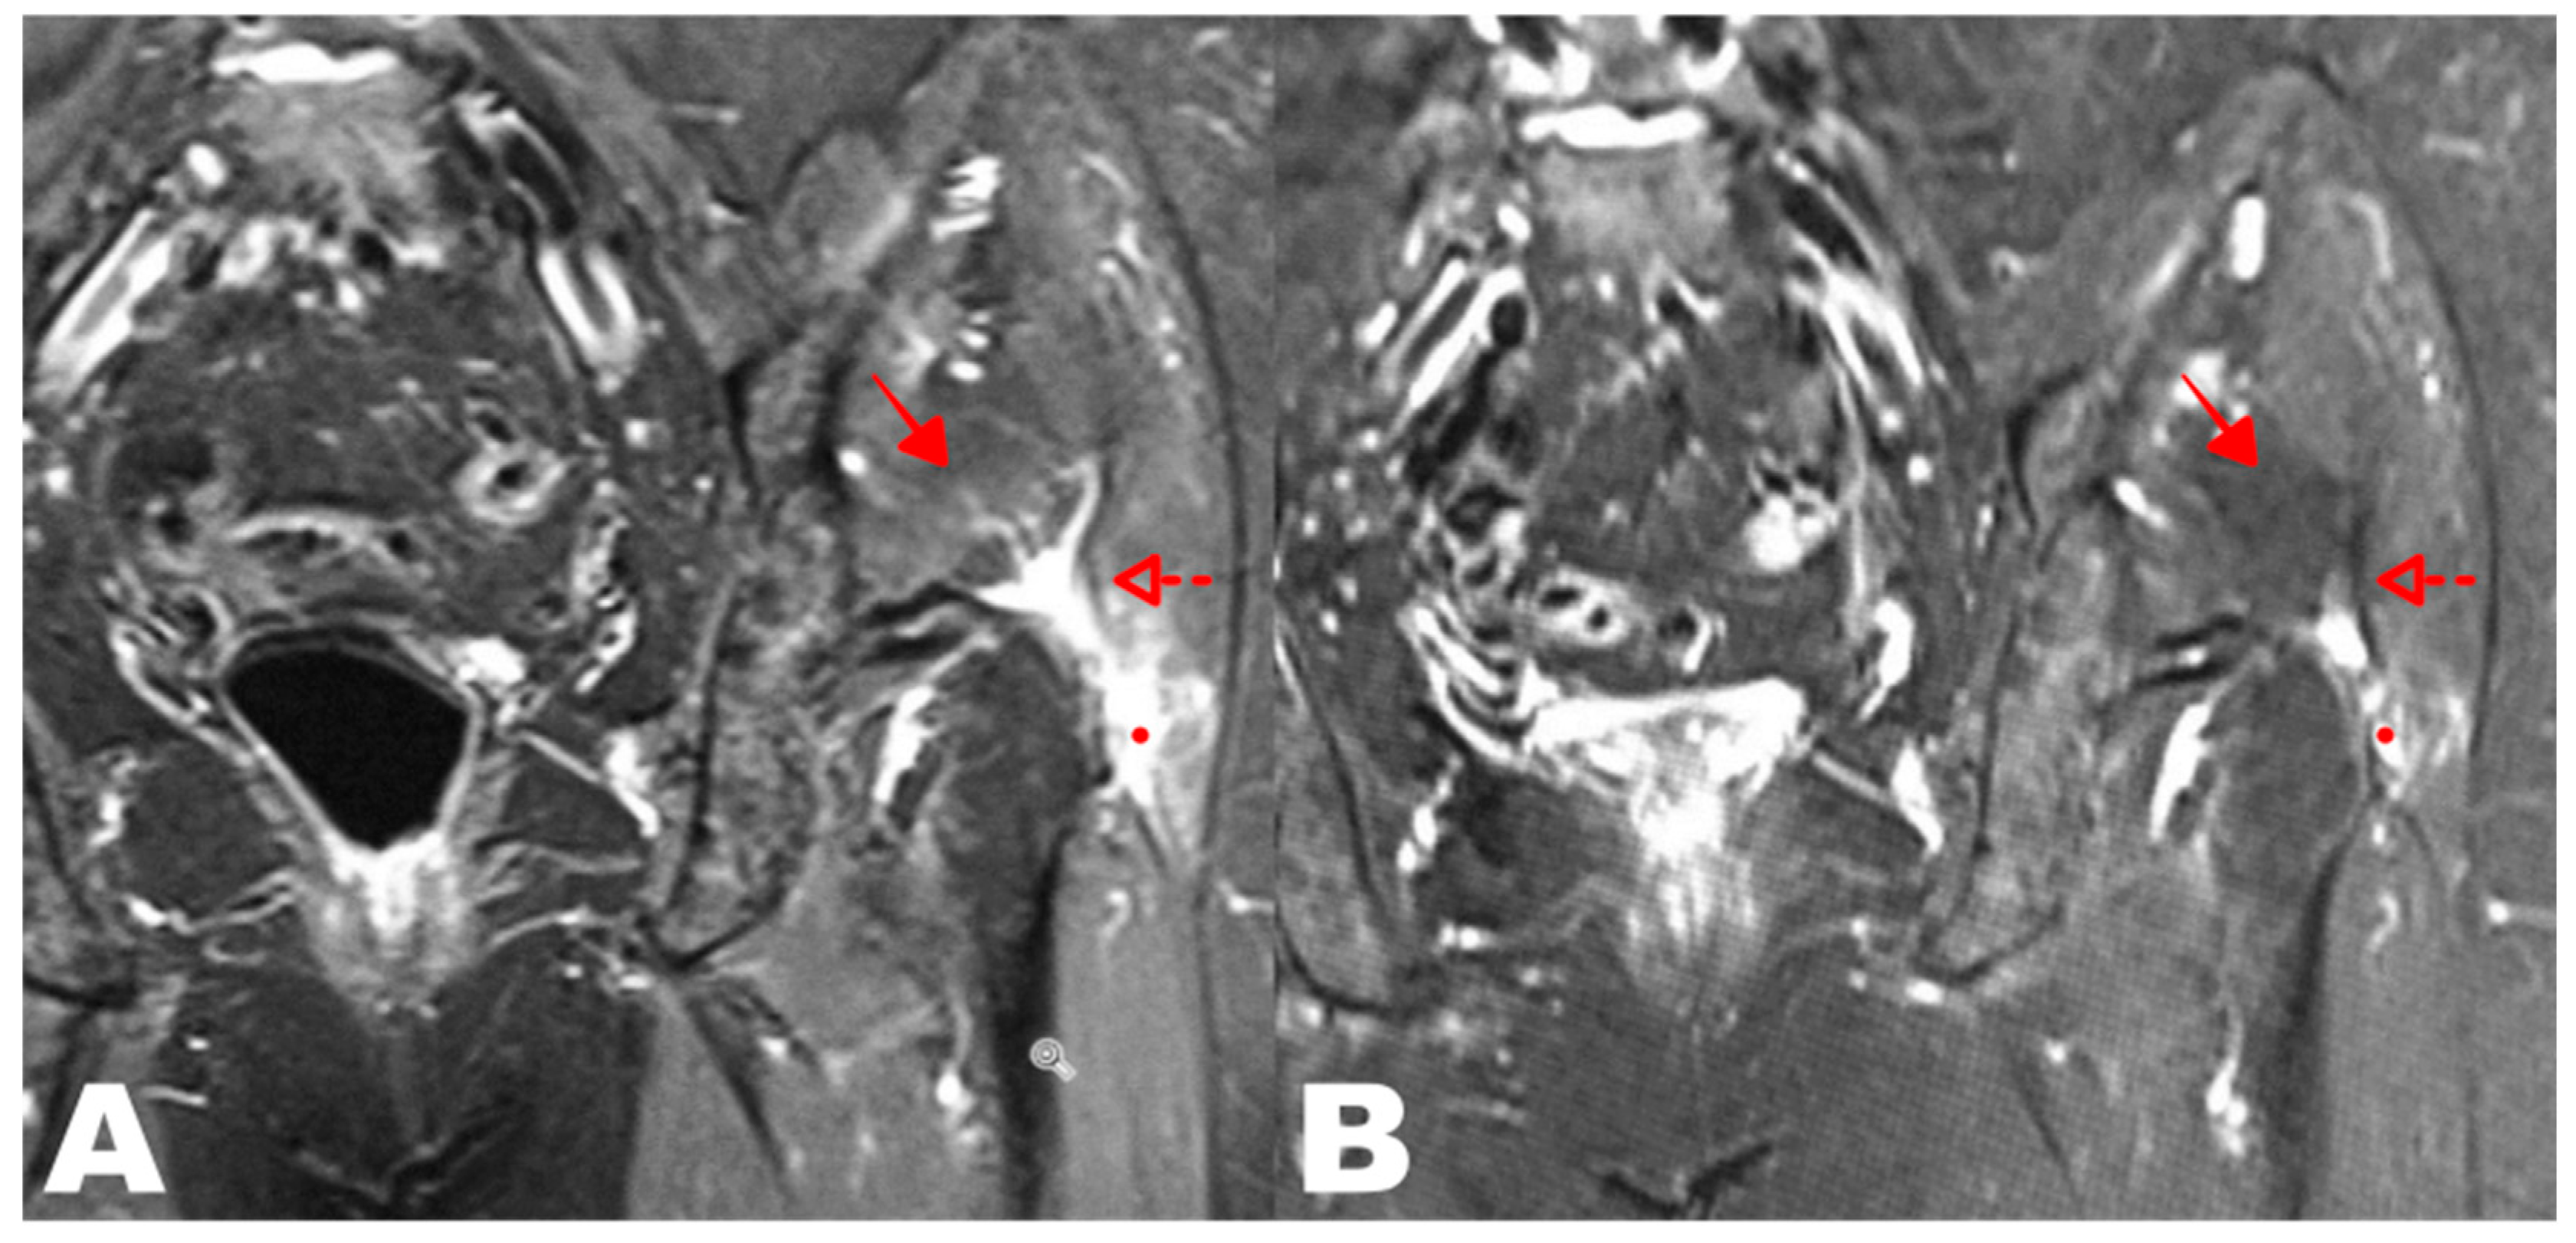

3.2.6. MRI Evaluation at 24 Weeks Compared to Baseline

| MRI DATA TABLE | |||

|---|---|---|---|

| 40 Subjects Evaluated | Improved | Unchanged | p Value |

| MRI T24w/FU vs. T0 | 28 subjects (70%) | 12 subjects (30%) | p < 0.0001 |